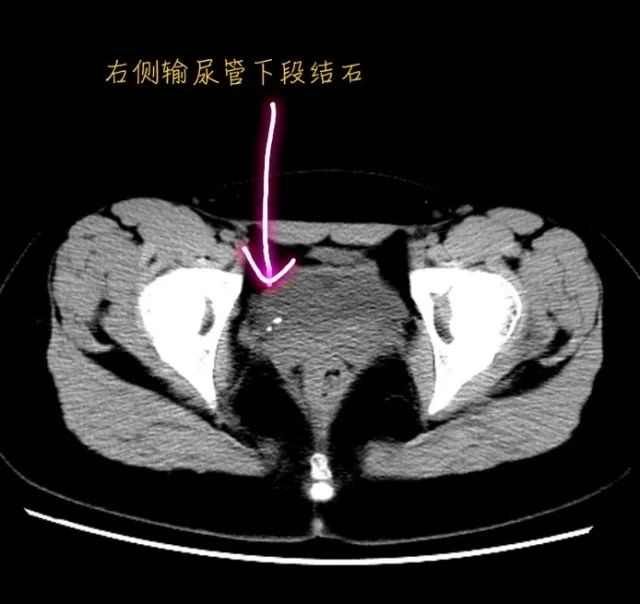

泌尿外科主任王新红结合CT图像判断右侧小肾积水伴输尿管结石是由严重肾积水持续数天所致。泌尿科团队立即安排小珂接受输尿管镜碎石术,仅用了10多分钟就解除了她的病痛。